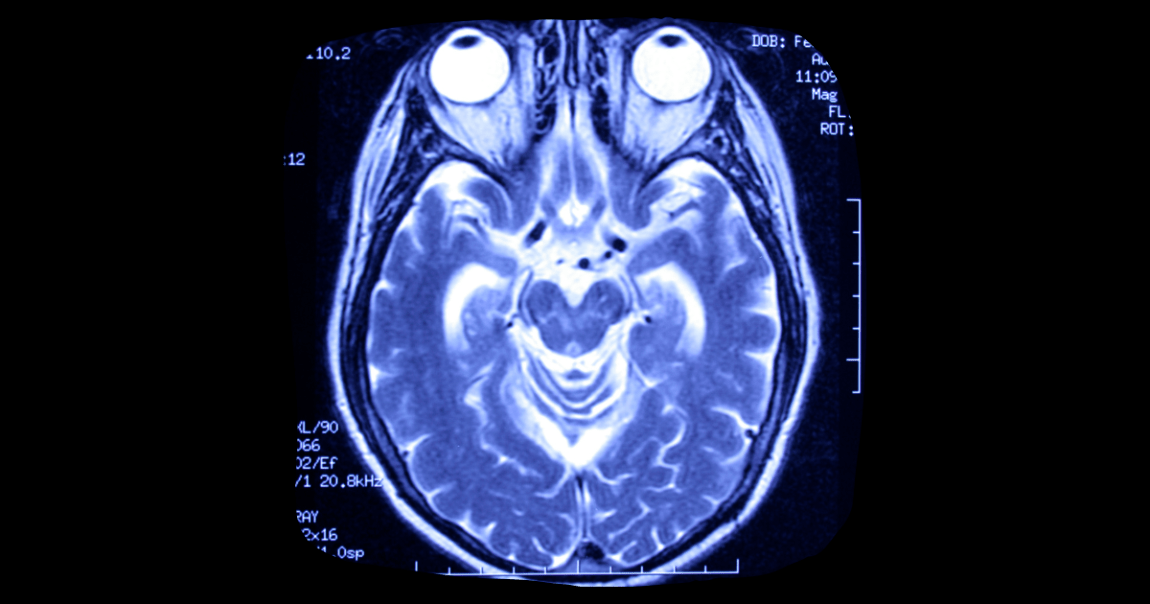

Yesterday’s Daily Beast report detailed just how hard it is to legally define death, which before 1959 was defined simply as the heart and lungs ceasing to function. But after French physicians discovered “coma dépassé,” which means “beyond a coma,” legal clarification was written allowing doctors and hospitals to complete organ donations from these types of patients in order to save other patients’ lives.

But what if brain death is reversible, or not 100 percent complete? Thaddeus Pope of the Mitchell Hamline School of Law says these conversations start to revolve around which lives are most valuable and that gets into stick territory.

Other doctors point out cases like that of a 4-year-old boy who went through a stunted kind of puberty even though he was on life support for 20 years. Puberty is a hormonal process controlled by the brain, giving credence to the idea that the person is still somewhat alive — or mostly dead, depending on how you look at it.